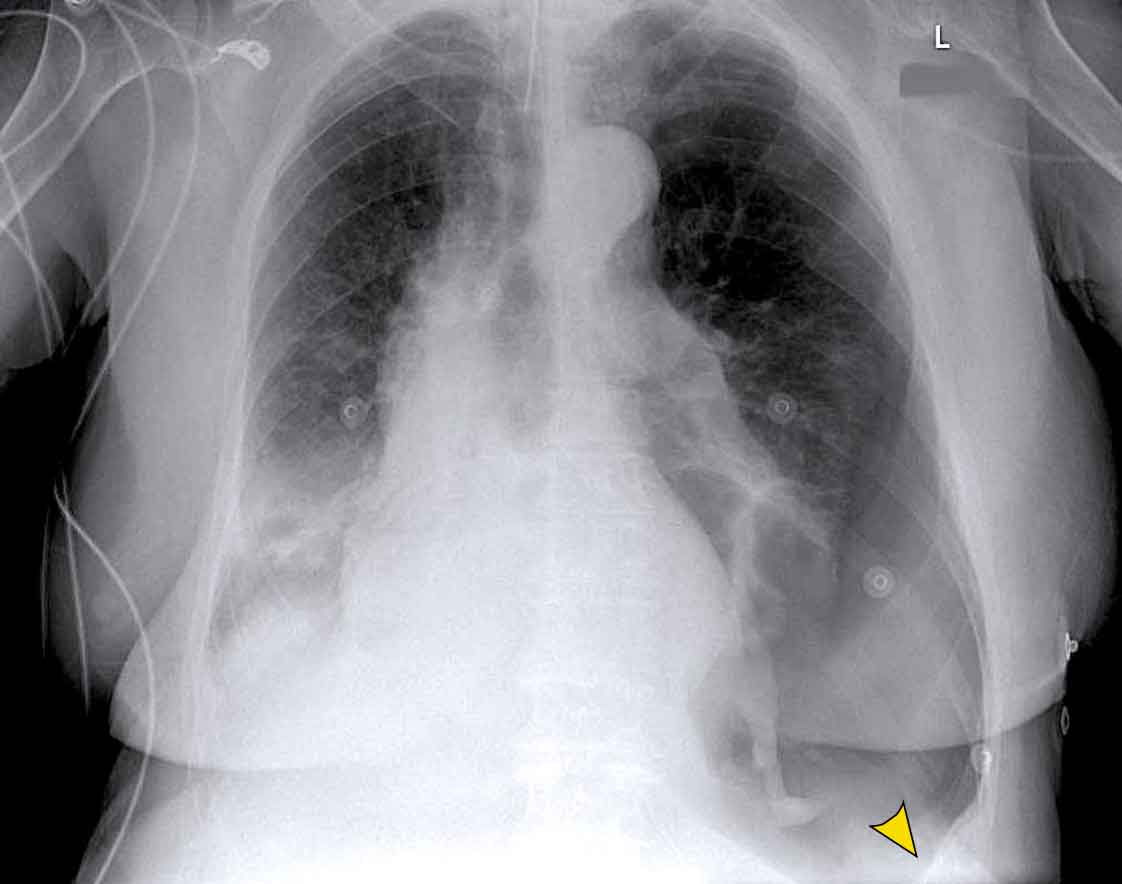

Pericardial effusion

When encountering an enlarged cardiac silhouette on chest radiography, it is essential to consider pericardial effusion as a potential mimic of cardiomegaly.

Case Example 1: Pericardial Effusion Mimicking Cardiomegaly

• On the chest radiograph, the patient appears to have a dilated heart.

• However, CT imaging clearly demonstrates that the apparent enlargement is due to significant pericardial fluid accumulation, not true myocardial chamber enlargement.

Case Example 3: Valve Replacement & Heart Failure

Post-valve replacement, a patient presents with a markedly enlarged cardiac silhouette on chest X-ray.

Findings

• A large cardiac silhouette

• There is evidence of pulmonary vascular redistribution, suggesting congestive heart failure.